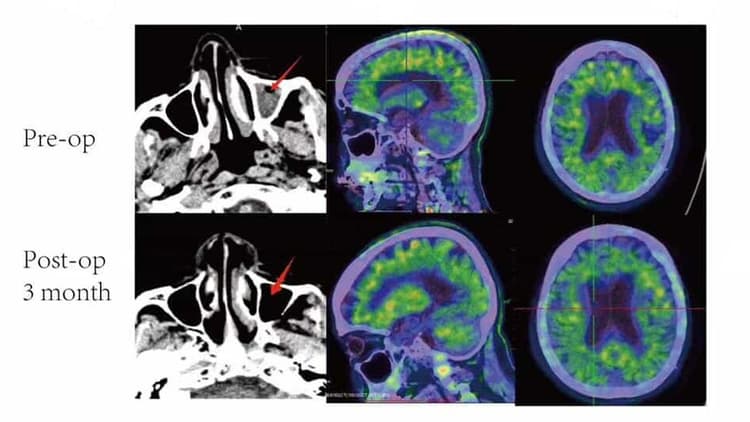

Brain Region Analysis Results

The left chart is the amyloid reduction after DC-LVA after 3 months. The right cart shows the CAT scan results before and 3 months after surgery. These promising results fuels our research and confidence in the procedure. Additionally, check out other stories from our patients.